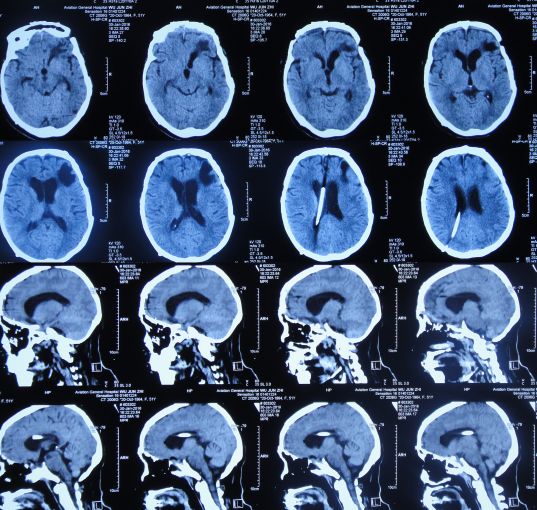

患者女,50岁,安徽省淮北市人。2014年12月14日,患者因高处坠落伤(2米左右)伤及头胸部及四肢,致昏迷,左耳、左鼻流血性液体,急诊前往安徽省淮南市潘集区某医院急查头CT显示左额叶脑挫伤、左侧颞骨凹陷性骨折、脑肿胀、颅内积气(图1);眼眶CT显示双侧眼眶内侧壁骨折(图2);胸部CT显示左侧肋骨骨折伴肺挫伤;右上肢X片显示右桡骨远端粉碎性骨折;左肩部X片显示左侧锁骨骨折。立即给予住院,保守治疗。

图1:2014年12月14日头CT:左额叶脑挫伤、左侧颞骨凹陷性骨折、脑肿胀、颅内积气

入院后第一天即2014年12月15日,患者神清,出现左眼肿胀,视力消失,左眼瞳孔增大,对光反射消失,左侧外耳道见澄清液体溢出,复查头CT:左额叶脑挫伤较前加重(图3)。

图3:2014年12月15日头CT:左额叶脑挫伤较前加重